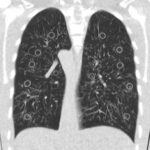

Radiation dose is an increasing concern, especially in the chest, and this area allows very significant dose reduction, preserving diagnostic capability. The comparison with chest X-Rays is more and more valid. Article: Dose estimation of ultra-low-dose chest CT to...